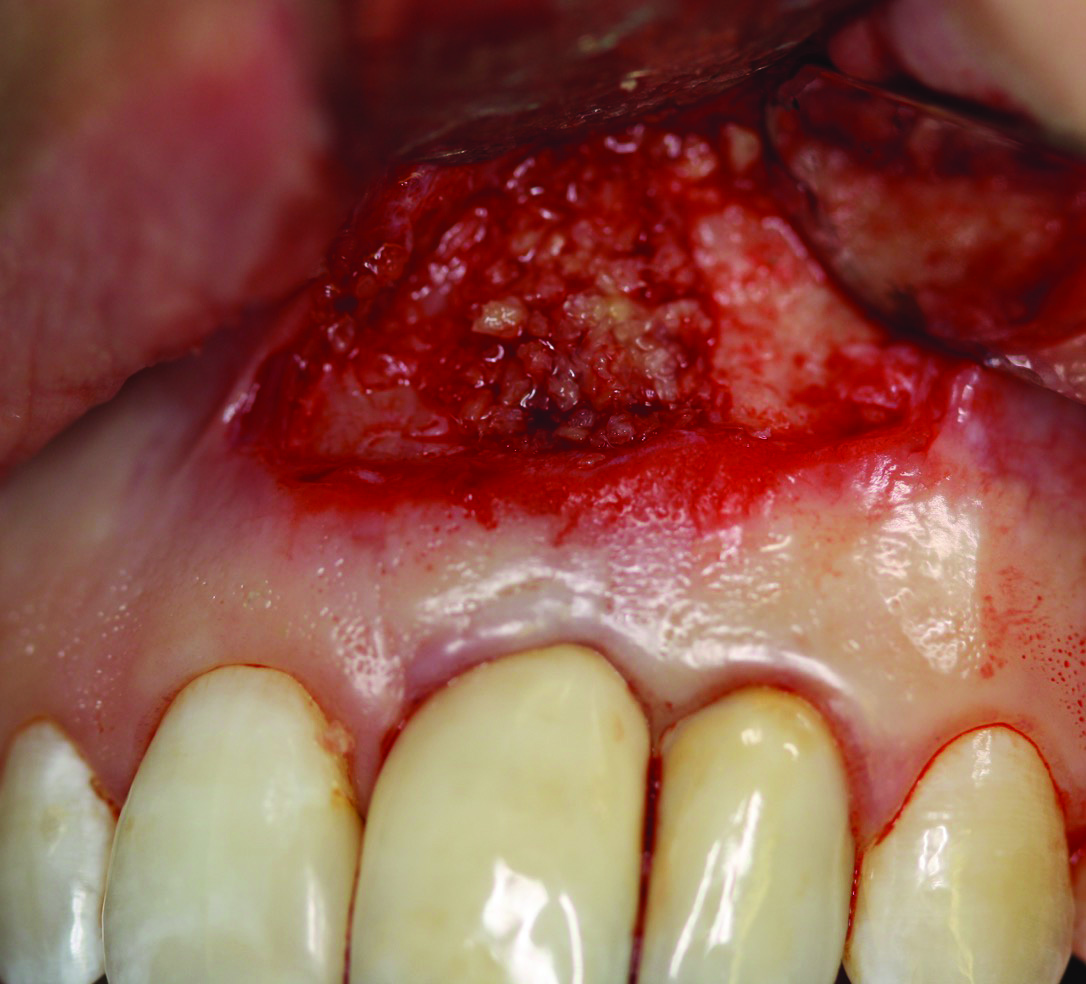

Fig 9. Case 2: Full-thickness flap reflection, extraction of tooth No. 5, debridement and cleaning of implant No. 6 with titanium scalers and titanium brush with doxycycline–saline slurry. Note extensive implant thread exposure approaching the apex. No mobility of the implant was noted.

Figure 9